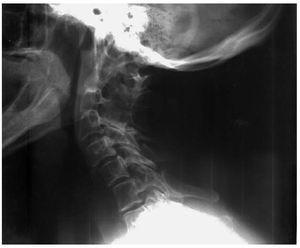

Figura 1. Radiografía lateral de columna cervical con sinostosis en C2-C3-C4.

Con la sospecha de patología atlantoaxoidea se solicita radiografía cervical, apreciándose en la proyección lateral (fig. 1) fusión de las articulaciones interapofisarias posteriores y bloque C2-C4, con lo que se establece la sospecha diagnóstica de síndrome de Klippel-Feil. Se realiza tomografía axial computarizada (TAC), donde se describe fusión occipitoatlantoidea, fusión de los cuerpos vertebrales y de los elementos posteriores de C2, C3 y C4, atrofia de los discos intervertebrales y disminución del diámetro anteroposterior de los cuerpos vertebrales. Ante los hallazgos de la TAC se recomienda realizar una resonancia magnética (RM) para estudiar el canal medular. En la RM (fig. 2) se observa acentuación de la lordosis en los niveles C2 - C3 - C4 asociada a fusión parcial de dichos cuerpos vertebrales con hipoplasia relativa de los mismos; se excluyen compromisos mecánicos extrínsecos sobre la unión bulbomedular o cordón medular. La RM confirma la existencia de síndrome de Klippel-Feil tipo 2 sin compromiso neurológico.